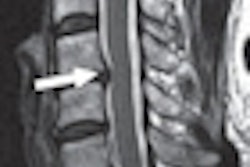

The most common abnormalities were congenital malformations with the potential to cause spinal cord damage. More severe curvature of the middle spine and juvenile scoliosis developing before age 10 were associated with a higher rate of MRI abnormalities.